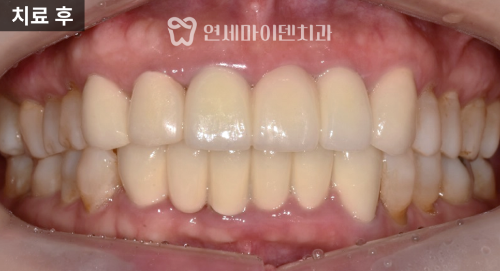

치료 결과

치료가 끝난 후 가장 큰 성과는

티가 나지 않는다는 점이었습니다.

임플란트 크라운과 자연 치아,

기존 크라운이 구분되지 않을 정도로

자연스럽게 완성되었습니다.

또한, 임시치아 단계에서도

불편 없이 생활할 수 있었기 때문에

심리적 부담도 크게 줄었습니다.

경과 관찰

치료 후 3년간 정기적으로 팔로업을 진행했으며,

임플란트·보철 모두 안정적으로 유지되고 있습니다.

잇몸 상태도 건강하게 관리되고 있고,

기능과 심미 두 가지 모두

안정적인 결과를 보이고 있습니다.